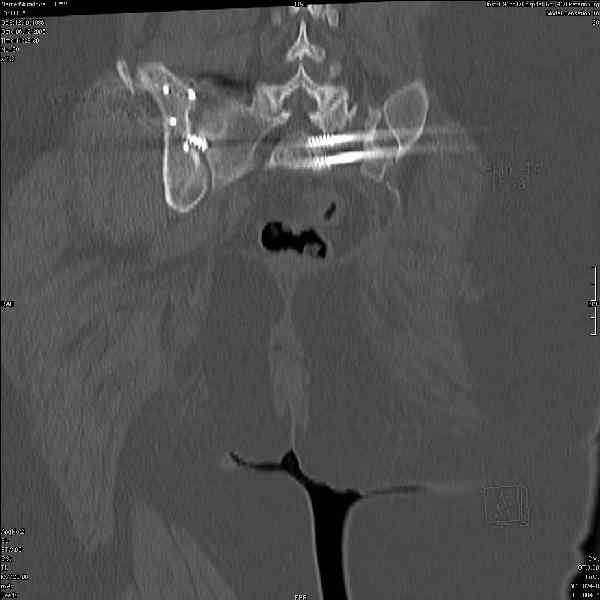

Молодая девушка 19 лет, травма 1 год назад, тогда же прооперирована.

В настоящее время имеются ноющие боли в области крестца слева, нарушение походки, ощущение неуверенности, слабости в левой нижней конечности, неврологически -непостоянные парестезии в левой нижней конечности. Ходит с дополнительной опорой, страдает от ожирения.

Какова по вашему будет оптимальная тактика в отношении несращения крестца? Замена винтов на более длинные с коррекцией их положения+ туннелизация зоны нестращения, открытое вмешательство с костной аутопластикой или еще какие варианты?

В приложении снимки при поступлении и послеоперационные год назад.

Могу сказать одно: миграция винтов и нестабильность синтеза левого подвздошно-крестцовогоо сочленения очевидна.

были использованы винты 7.2 мм, кроме того иетодика транссакральной фиксации не является общепринятой и широко рекомендуемой, но и в этих случаях они наблюдали случаи вторичного смещения